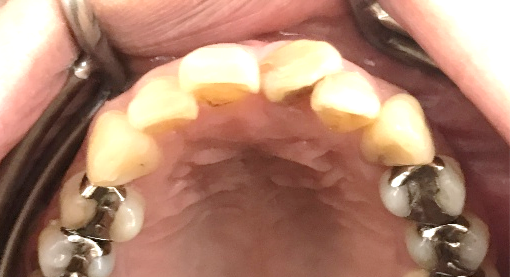

女性 Mさん 40代 (オールセラミック冠)

主訴

上の前歯をきれいにしたい。

治療内容

前歯4本を根管治療をし、オールセラミック冠を被せました。

所感

右の1本は、被せ物をしていましたが、すり減り形が変わり、変色もしていました。他の3本はすでに神経がない状態で、詰め物をしていましたが、詰め物及び歯自体も変色し、詰め物と自分の歯の境目のところからむし歯になっていました。治療後「きれいになって嬉しいです。治療して本当に良かったです。」と、とても喜んでくださいました。

オールセラミック冠4本:¥104,500×4本=¥418,000(税込)

Before

After